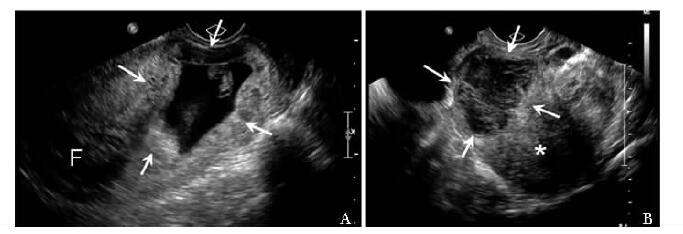

方法  收集2011年11月至2013年1月北京协和医院临床确诊为剖宫产切口瘢痕妊娠、并接受手术治疗的35例患者, 术前进行二维及三维超声检查, 获得病灶最大径、病灶平均径、病灶植入瘢痕面积、植入体积及植入深度; 按有无胎心搏动、病灶类型、彩色多普勒血流分级及术前有/无甲氨蝶呤联合治疗进行分组。记录患者手术中出血量, 分析超声参数与出血量的相关性, 比较组间出血量差异; 将病灶按出血量进行分组, ≥ 200 ml组和 < 200 ml组, 应用Logistic回归分析影响出血量的独立危险因素。

Methods  A total of 35 CSP patients who received operational treatment from November 2011 to January 2013 were enrolled in this study. The 2-and 3-dimensional ultrasound examinations were performed before the surgery, and the following parameters were recorded:maximum diameter of lesion(Dmax), average diameter of lesion(Dmean), implantation area of lesion(S), implantation volume of lesion(V), and implantation depth of lesion(Dimp). All these cases were divided into different groups according to the following characteristics separately:with/without fetal heart beat, lesion shown as gestational sac/mass, vasculature grade poor/median/rich, whetheror not combined with methotrexate(MTX) treatment prior to operations. The amount of bleeding during the operation was recorded. The correlation between the above parameters and the amount of intraoperative bleeding was analyzed. The bleeding amount of different groups was compared. Also, the patients were divided into two groups according to bleeding amount ≥ 200 ml and < 200 ml, and the potential independent risk factors of bleeding were analyzed using Logistic regression.